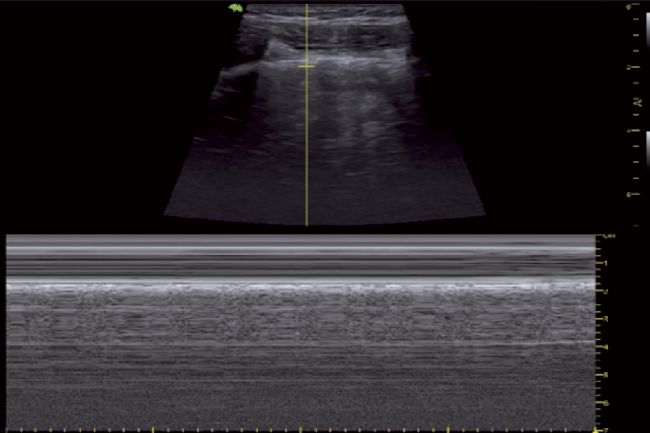

超聲波除了具有應(yīng)用于滅殺病毒的可能性,目前其在病毒的醫(yī)療診斷治療領(lǐng)域或是各種微生物實(shí)驗(yàn)研究中也有著相當(dāng)廣泛的應(yīng)用。比如當(dāng)前新冠病毒的監(jiān)測診斷領(lǐng)域中必要的超聲成像技術(shù),其可以為臨床醫(yī)生及時(shí)提供患者的各種重要生命體征,在急性重癥肺炎的診斷、治療以及療效評(píng)估上具有不可替代的地位。

正常肺超聲M型圖像(沙灘樣征)

肺炎患者M(jìn)型超聲圖像(平流層征)